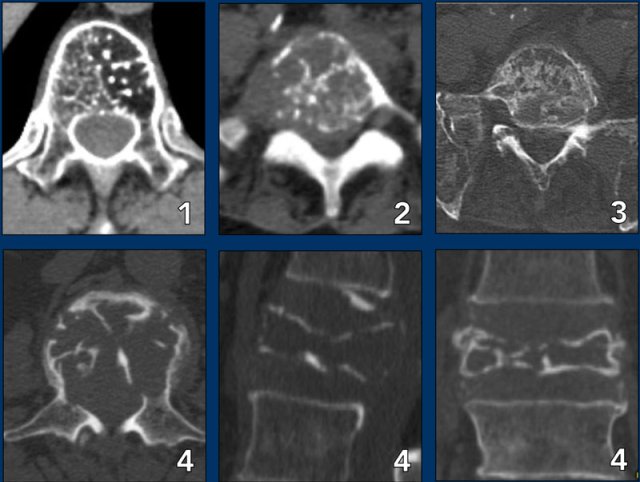

Polyostotic or multiple lesions

Most bone tumors are solitary lesions.

If there are multiple or polyostotic lesions, the differential diagnosis must be adjusted.

Polyostotic lesions

NOF, fibrous dysplasia, multifocal osteomyelitis, enchondromas, osteochondoma, leukemia and metastatic Ewing' s sarcoma.

Multiple enchondromas are seen in Morbus Ollier.

Multiple enchondromas and hemangiomas are seen in Maffucci's syndrome.

Polyostotic lesions > 30 years

Common: Metastases, multiple myeloma, multiple enchondromas.

Less common: Fibrous dysplasia, Brown tumors of hyperparathyroidism, bone infarcts.

Mnemonic for multiple oseolytic lesions: FEEMHI:

Fibrous dysplasia, enchondromas, EG, Mets and myeloma, Hyperparathyroidism, Infection.